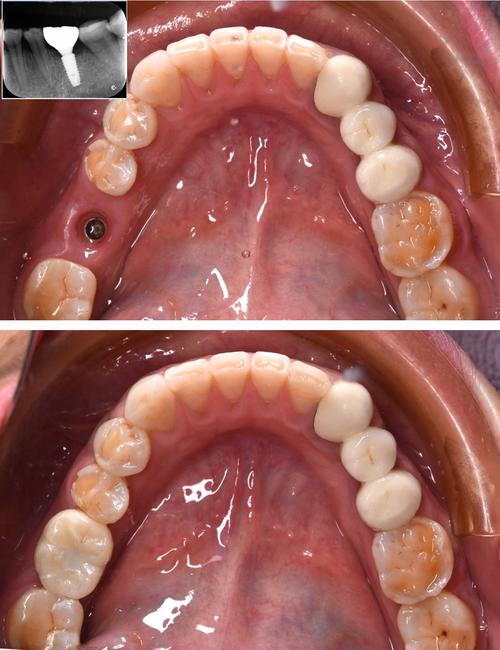

种植体周围炎是种植术后最常见的并发症之一,指种植体周围支持组织发生的炎症,与天然牙的牙周炎病理过程相似,但危害更大,未治疗的牙周病患者口腔内本身存在大量致病菌,种植手术会进一步破坏局部黏膜屏障,细菌易侵入种植体与牙槽骨的界面(种植体-骨结合界面),引发炎症,临床表现为种植体周围牙龈红肿、出血、溢脓,牙周袋形成,X光片显示牙槽骨进行性吸收,最终导致种植体松动、脱落,研究显示,未接受牙周治疗的种植患者,种植体周围炎的发生率比牙周健康者高3-5倍,且病情进展更快,治疗难度更大。

牙周治疗稳定后(通常需3-6个月的维护期,定期复查每3-4个月一次),再次评估牙槽骨量、牙周状况,若牙槽骨量充足(种植区骨高度≥10mm,厚度≥5mm),无活动性炎症,方可进行种植手术,若骨量不足,需先植骨,待骨愈合后再种植。